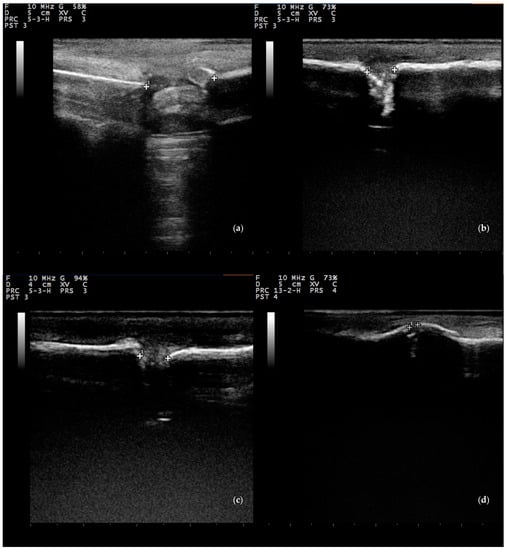

3.3.2. Ultrasonographic Examination

- Maffulli, N.; Thornton, A. Ultrasonographic appearance of external callus in long-bone fractures. Injury 1995, 26, 5–12. [Google Scholar] [CrossRef]

- Risselada, M.; Kramer, M.; De Rooster, H.; Taeymans, O.; Verleyen, P.; Van Bree, H. Ultrasonographic and radiographic assessment of uncomplicated secondary fracture healing of long bones in dogs and cats. Vet. Surg. 2005, 34, 99–107. [Google Scholar] [CrossRef] [PubMed]

- Risselada, M.; Van Bree, H.; Kramer, M.; Duchateau, L.; Verleyen, P.; Saunders, J.H. Ultrasonographic assessment of fracture healing after plate osteosynthesis. Vet. Radiol. Ultrasound 2007, 48, 368–372. [Google Scholar] [CrossRef]

- Caruso, G.; Lagalla, R.; Derchi, L.; Iovane, A.; Sanfilippo, A. Monitoring of fracture calluses with color doppler sonography. J. Clin. Ultrasound 2000, 28, 20–27. [Google Scholar] [CrossRef]